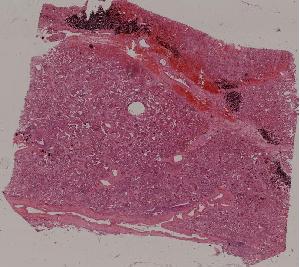

62.急性普通型病毒性肝炎

63.慢性活动性肝炎

64.急性重型病毒性肝炎

65.亚急性重型病毒性肝炎

66.活动性结节性肝硬化

67.非活动性结节性肝硬化

68.胆汁性肝硬化

69.肝细胞性肝癌

72.膜性肾小球肾炎

73.急性肾小球肾炎

74.新月体性肾炎

75.慢性硬化性肾小球肾炎